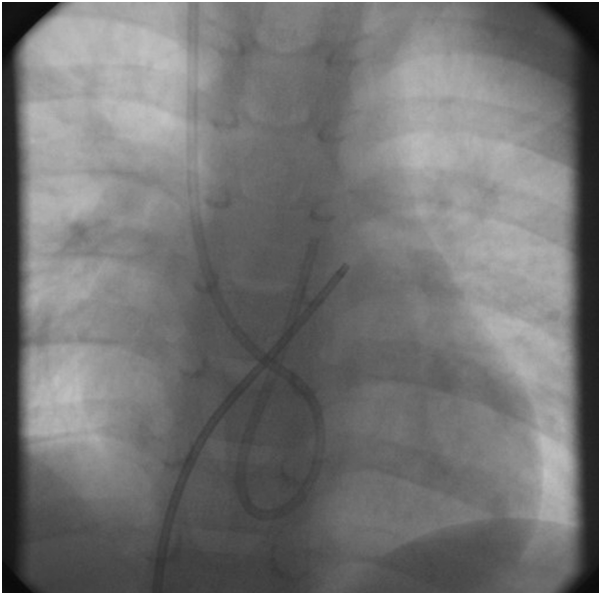

The child was electively intubated and ventilated with general anesthesia. Initial attempts at snaring the Port-A-Cath through the right internal jugular vein were not successful (Figure 4). Therefore, the heart was accessed through the right femoral vein with 6F pediatric introducer sheath. Then 6F CORDIS MPA2 catheter was used to cross to the right ventricle outflow tract where the tip of the Port-A-Cath was located (Figure 5).

Figure 4 Shows the migrated Port-A-Cath as well as an internal jugular vein catheter.

Figure 5 Locating the tip of the Port-A-Cath through the right ventricle outflow tract.